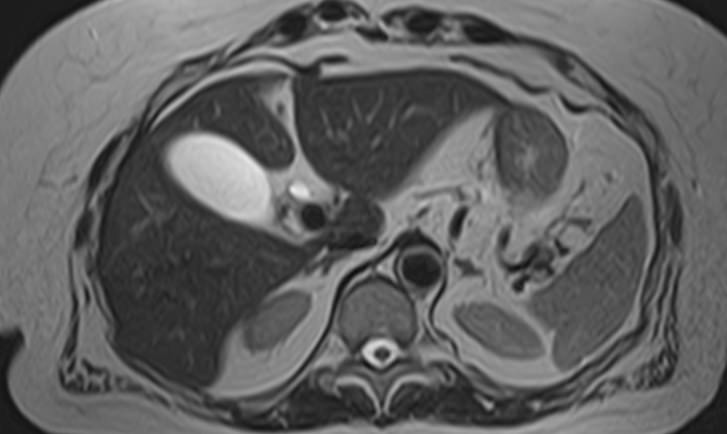

Исследование желчных протоков и пузыря методом МРТ помогает объективно оценить состояние билиарного тракта и выявить патологические изменения на ранних этапах развития. Исследование проводят при подозрении на инфекционный, воспалительный или опухолевый процесс, а также для исключения конкрементов. МР-диагностика позволяет определить локализацию и характер патологических изменений и установить окончательный диагноз.